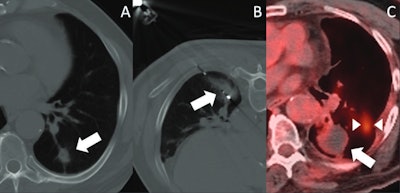

Images depict post-SBRT image-guided thermal ablation. (A) Axial CT image demonstrates a nodular recurrence of NSCLC at the site of prior SBRT in the left lower lobe (arrow). (B) Intraprocedural axial CT image shows placement of a microwave ablation probe within the recurrent tumor, with surrounding ground-glass opacity (arrow). (C) PET-CT obtained 14 months post-ablation demonstrates no significant FDG uptake within the treated lesion (arrow); however, a new site of disease is noted (between arrowheads).ARRS